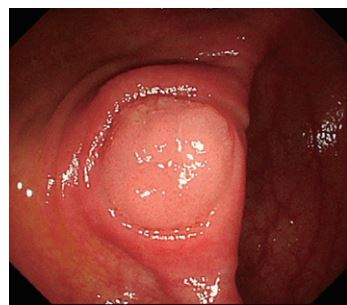

憩室内に早期癌が見つかることはよくあります(下記写真は憩室内に発生した粘膜内癌です。当院で見つかり、憩室反転下内視鏡切除で根治されました)。